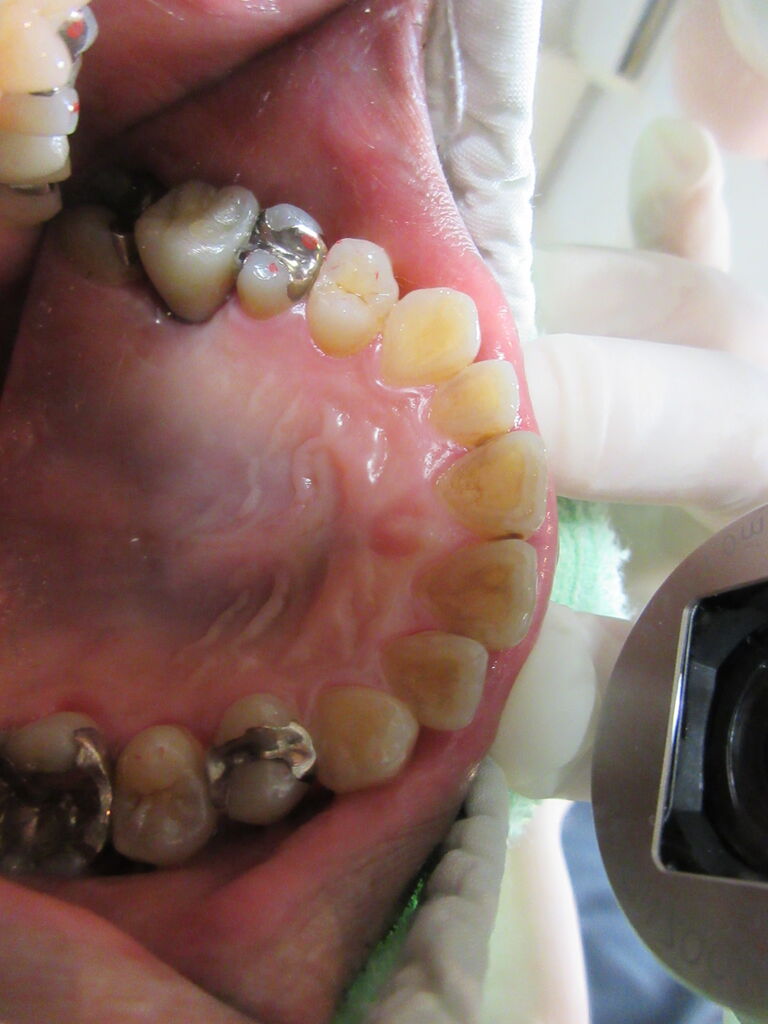

上顎左側第2小臼歯部にインプラント上部構造ジルコニア装着、6番がヘミセクションしているのであまり負担を掛けたくないためインプラント希望でした。